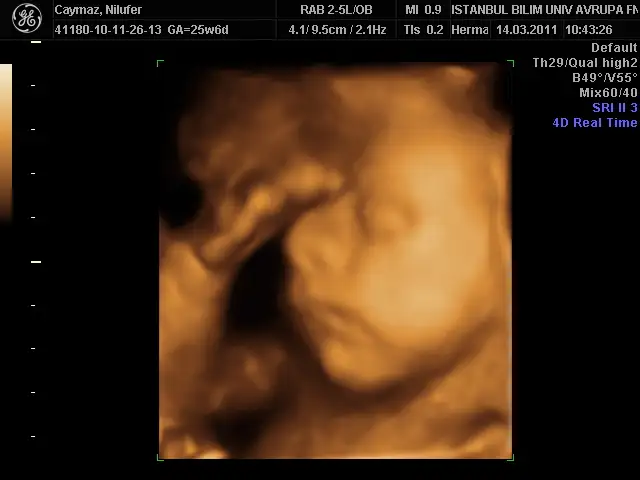

benimki 35 cm 1056 gr olmuş annesinin gülü dr önce rahmi çok ince budu 2,7 mm sonra sıkıştık tuvalalete öyle baktı çok şükür bir problem yokmuş bu sefer yüzünü bizden gizlemedi oğluşumm bence bana benziyor babasını kıl ediyorum bana benziyor diye kız olsa anlarım bana benzesin triplerini de diyor bu erkek banabenzicek diyo bi kıskanıyor bi kıskanıyor çok hoşuma gidiyorr

alın sıze teyzelerı suratsız oglum:))

yelkovan resimler super seninkisi pek dertli gorunuyor iceride bir buyuk devirmis gibi))) masallahhhhhhhhh